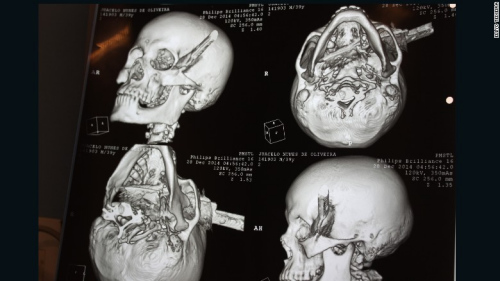

男子被人用刀刺中头部,直穿头骨。

中新网1月4日电 据外媒报道,巴西一名男子在与他人争吵过程中被人用刀刺中头部,直穿头骨。在经过2个半小时的手术后,该男子奇迹存活。

据报道,39岁受害男子系一名出租车司机,事发时他正在一个酒吧喝酒,结果与人发生口角。男子被刺中4刀,其中3刀刺中身体,1刀被插进头部,横穿过左眉骨。

医生说,刀已经完全穿过了男子的头部,几乎就要接近嗅觉神经,但仅仅破坏了部分味觉神经。男子几乎就要失去视觉、嗅觉和味觉,但是没想到,幸运的是他将毫发无损。